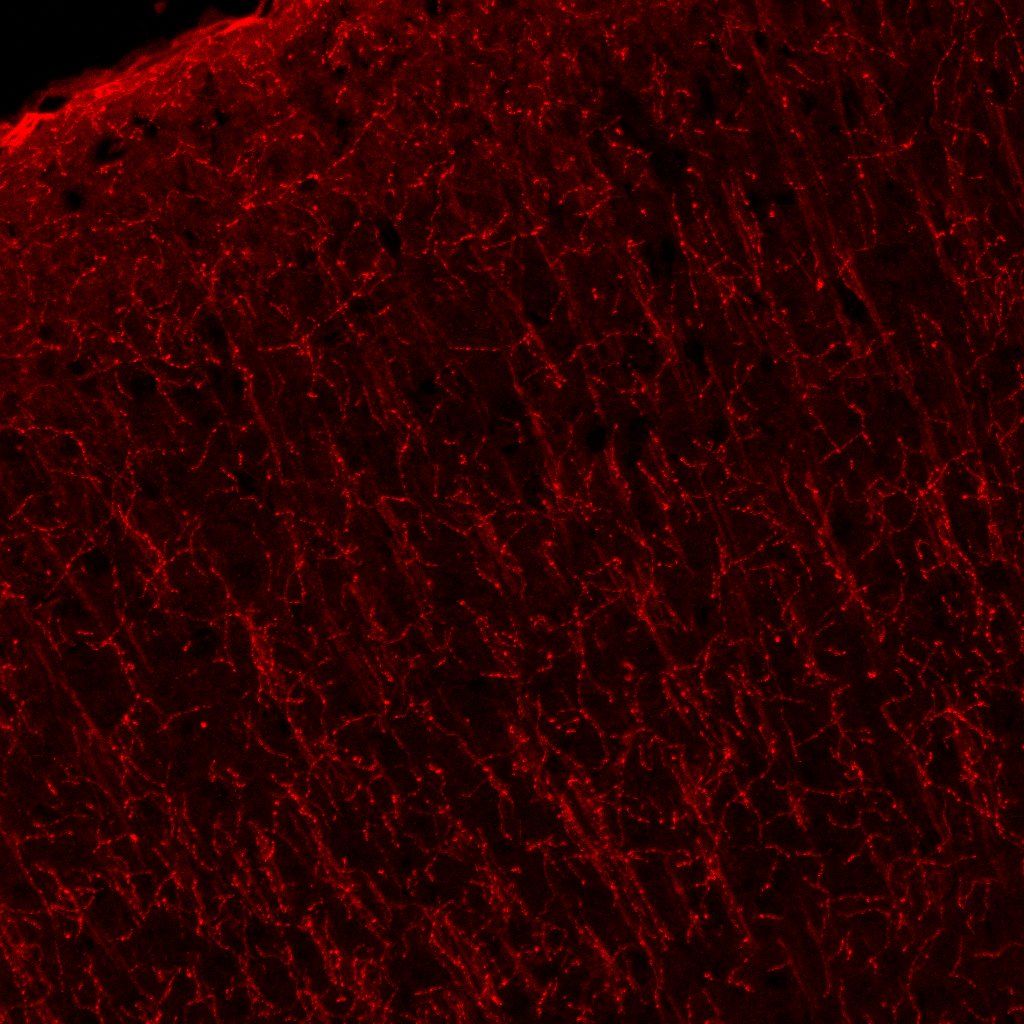

NGF R/TNFRSF16 in Mouse Brain. NGF R/TNFRSF16 was detected in perfusion fixed frozen sections of mouse brain (cortex) using 7 µg/mL Goat Anti-Mouse NGF R/TNFRSF16 Antigen Affinity-purified Polyclonal Antibody (Catalog # AF1157) overnight at 4 °C. Tissue was stained (red) and counterstained (green). View our protocol for Fluorescent IHC Staining of Frozen Tissue Sections.